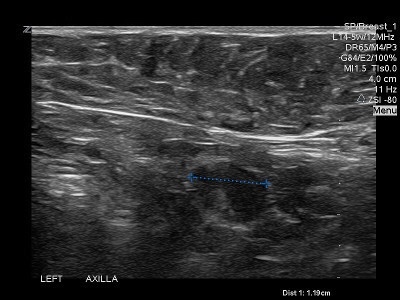

👉A normal axillary lymph node is elliptical in shape (or bean shaped) and has a narrow, symmetrical, hypoechoic cortex surrounding an isoechoic to hyperechoic fatty hilum (Image).

👉The cortex of a normal node is composed largely of lymphatic tissue and fluid-filled cortical sinuses, thus the hypoechoic echogenicity.

👉The hilum contains alternating medullary cords and sinusoids that have innumerable acoustic interfaces, thus the higher degree of echogenicity.